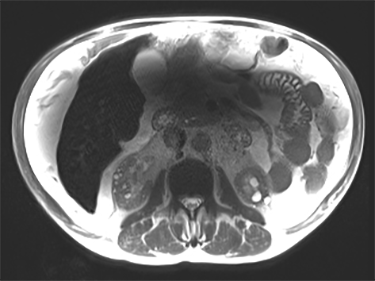

| Fat/Water Swap Areas that should appear fat suppressed are water suppressed, and ar-eas that should appear water suppressed are fat suppressed | ![]()

| Decreased linearity at the corners of the FOV corrupt the signal. The fat water identification algorithm may become confused, which results in a full series fat/water image swap. Phase wrap in slice and phase direction also influence swaps. This error may occur in regions of high magnetic field variation, in spatially isolated tissue, and/or in images with low signal-to-noise ratios, due to: